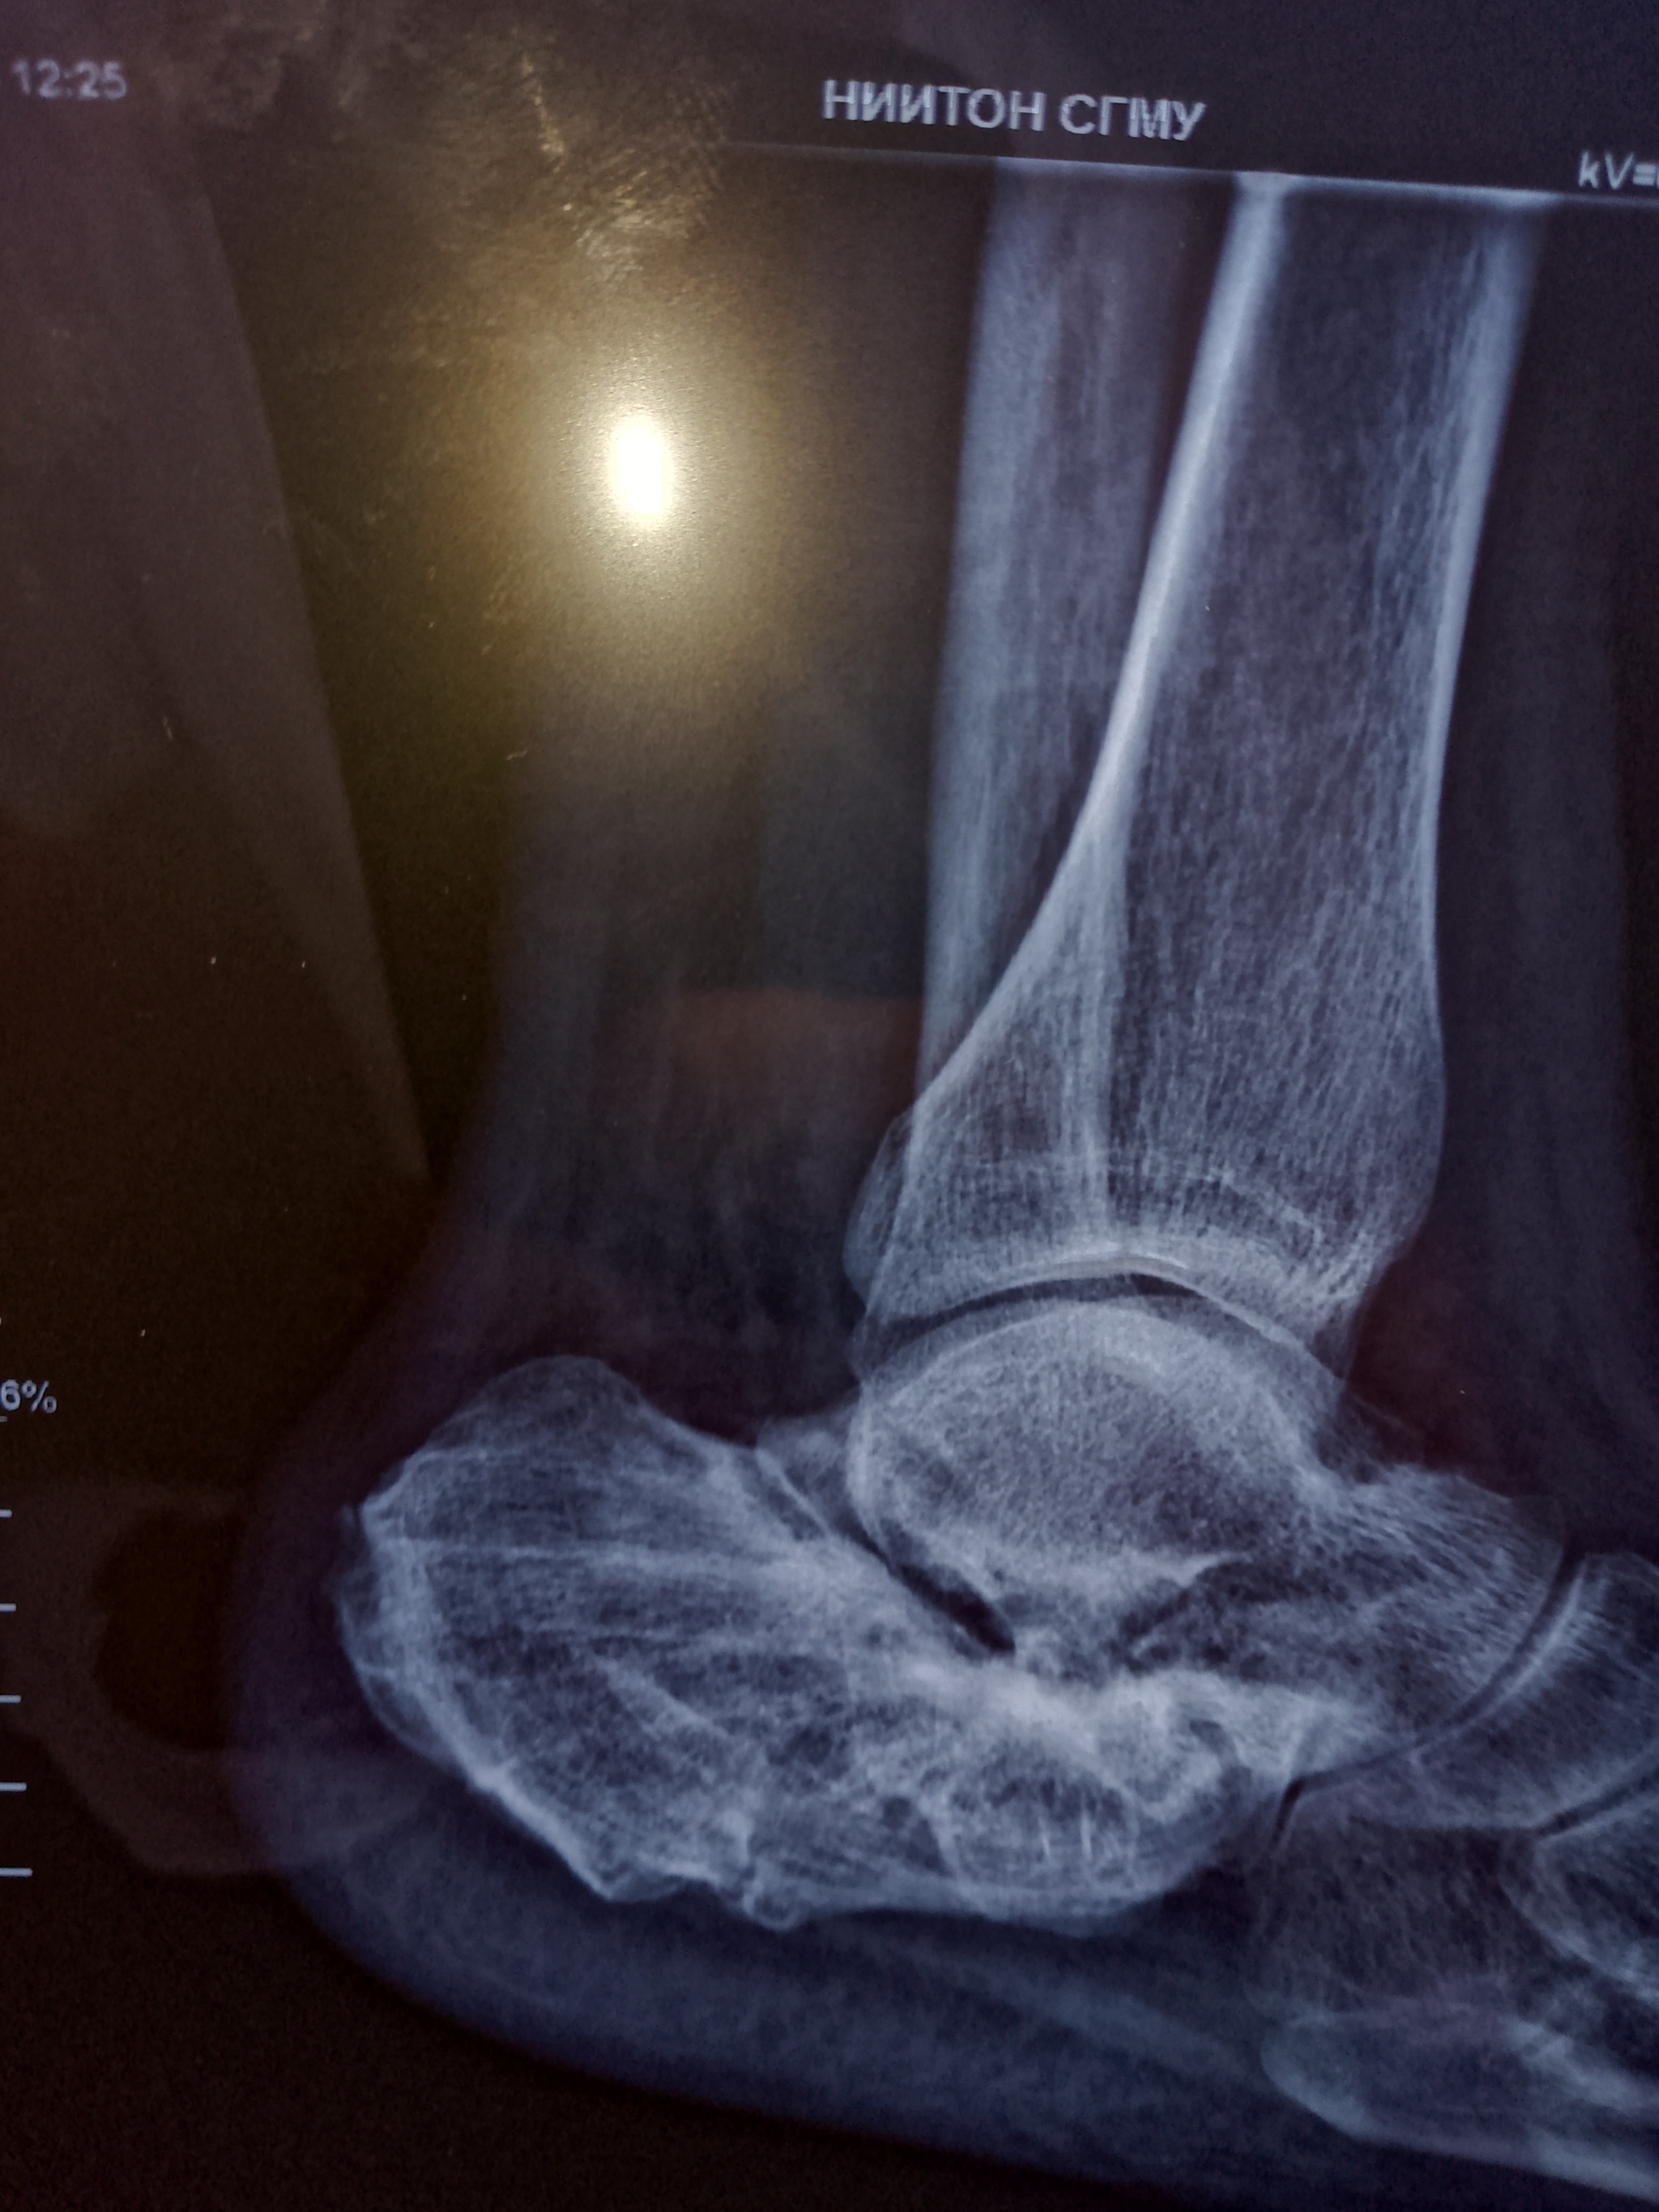

Итак, саморезы удалили. Нога по-прежнему болит. Болит с каждым шагом. Больше или меньше, в зависимости от погоды и нагрузки. Но болит при движении всегда и иногда в покое. Обращаюсь к силе Пикабу, посмотрите, пожалуйста, рентген. Есть шансы?